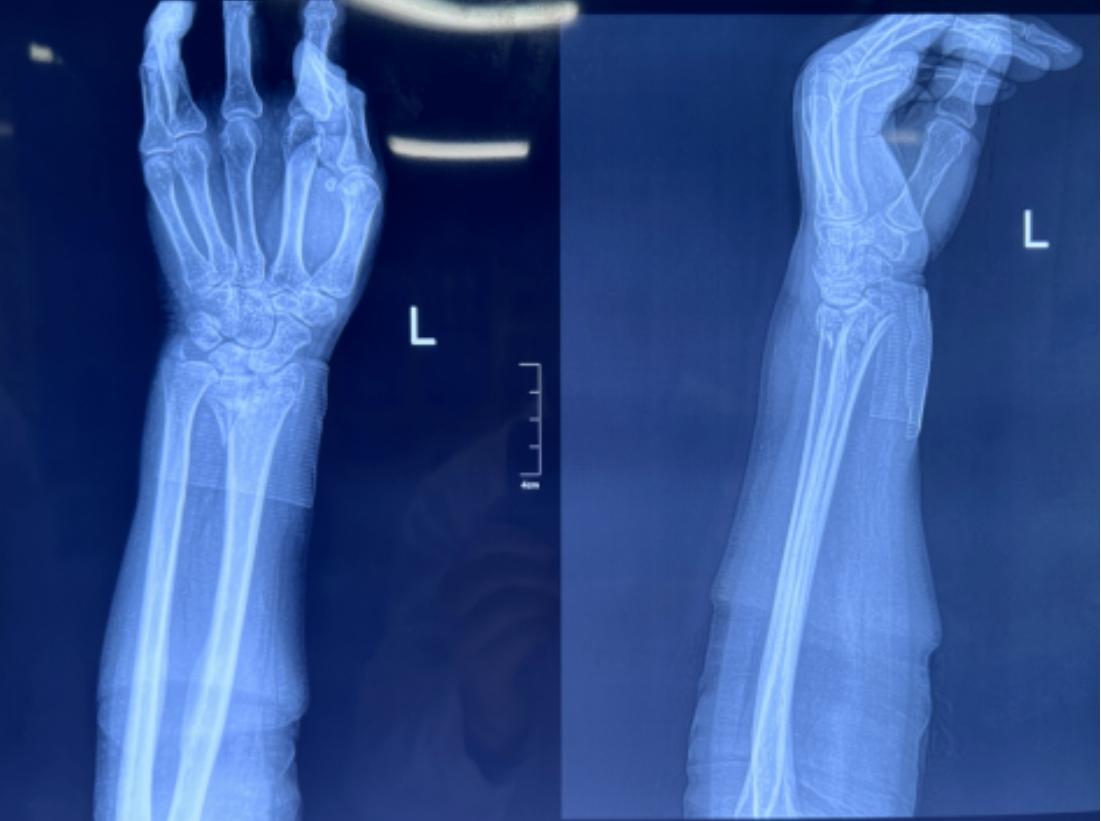

蓋氏骨折復(fù)位前 蓋氏骨折復(fù)位后